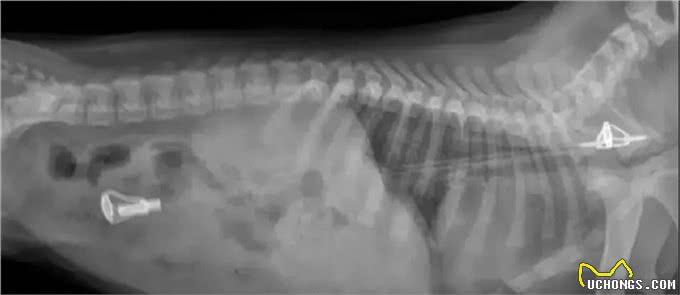

这只杜宾犬特别喜欢玩球,尤其是高尔夫球。

玩着玩着,主人发现球怎么越来越少了,后来发现高尔夫球全部跑到了小家伙的肚子里了,一共26枚。